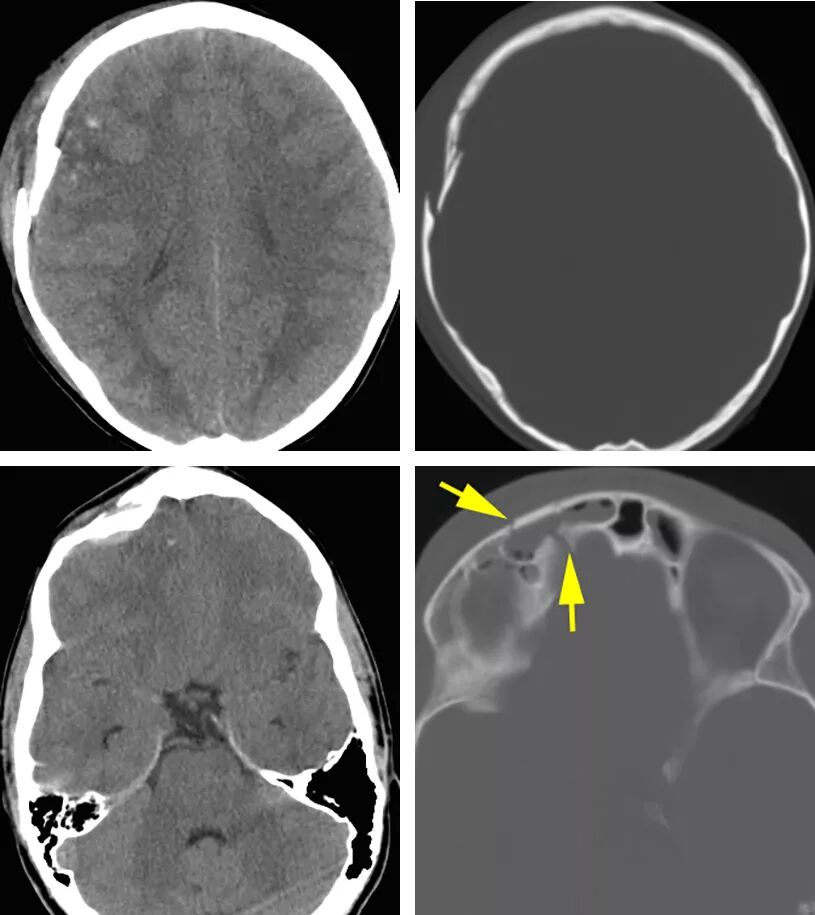

图1.CT平扫显示右侧额骨凹陷性骨折伴点状脑挫伤(上图)。骨折碎片凹陷超过颅骨厚度,硬膜损伤可能性高。下图展示的是一右侧额骨凹陷性骨折累及额窦前壁及后壁(箭头)。